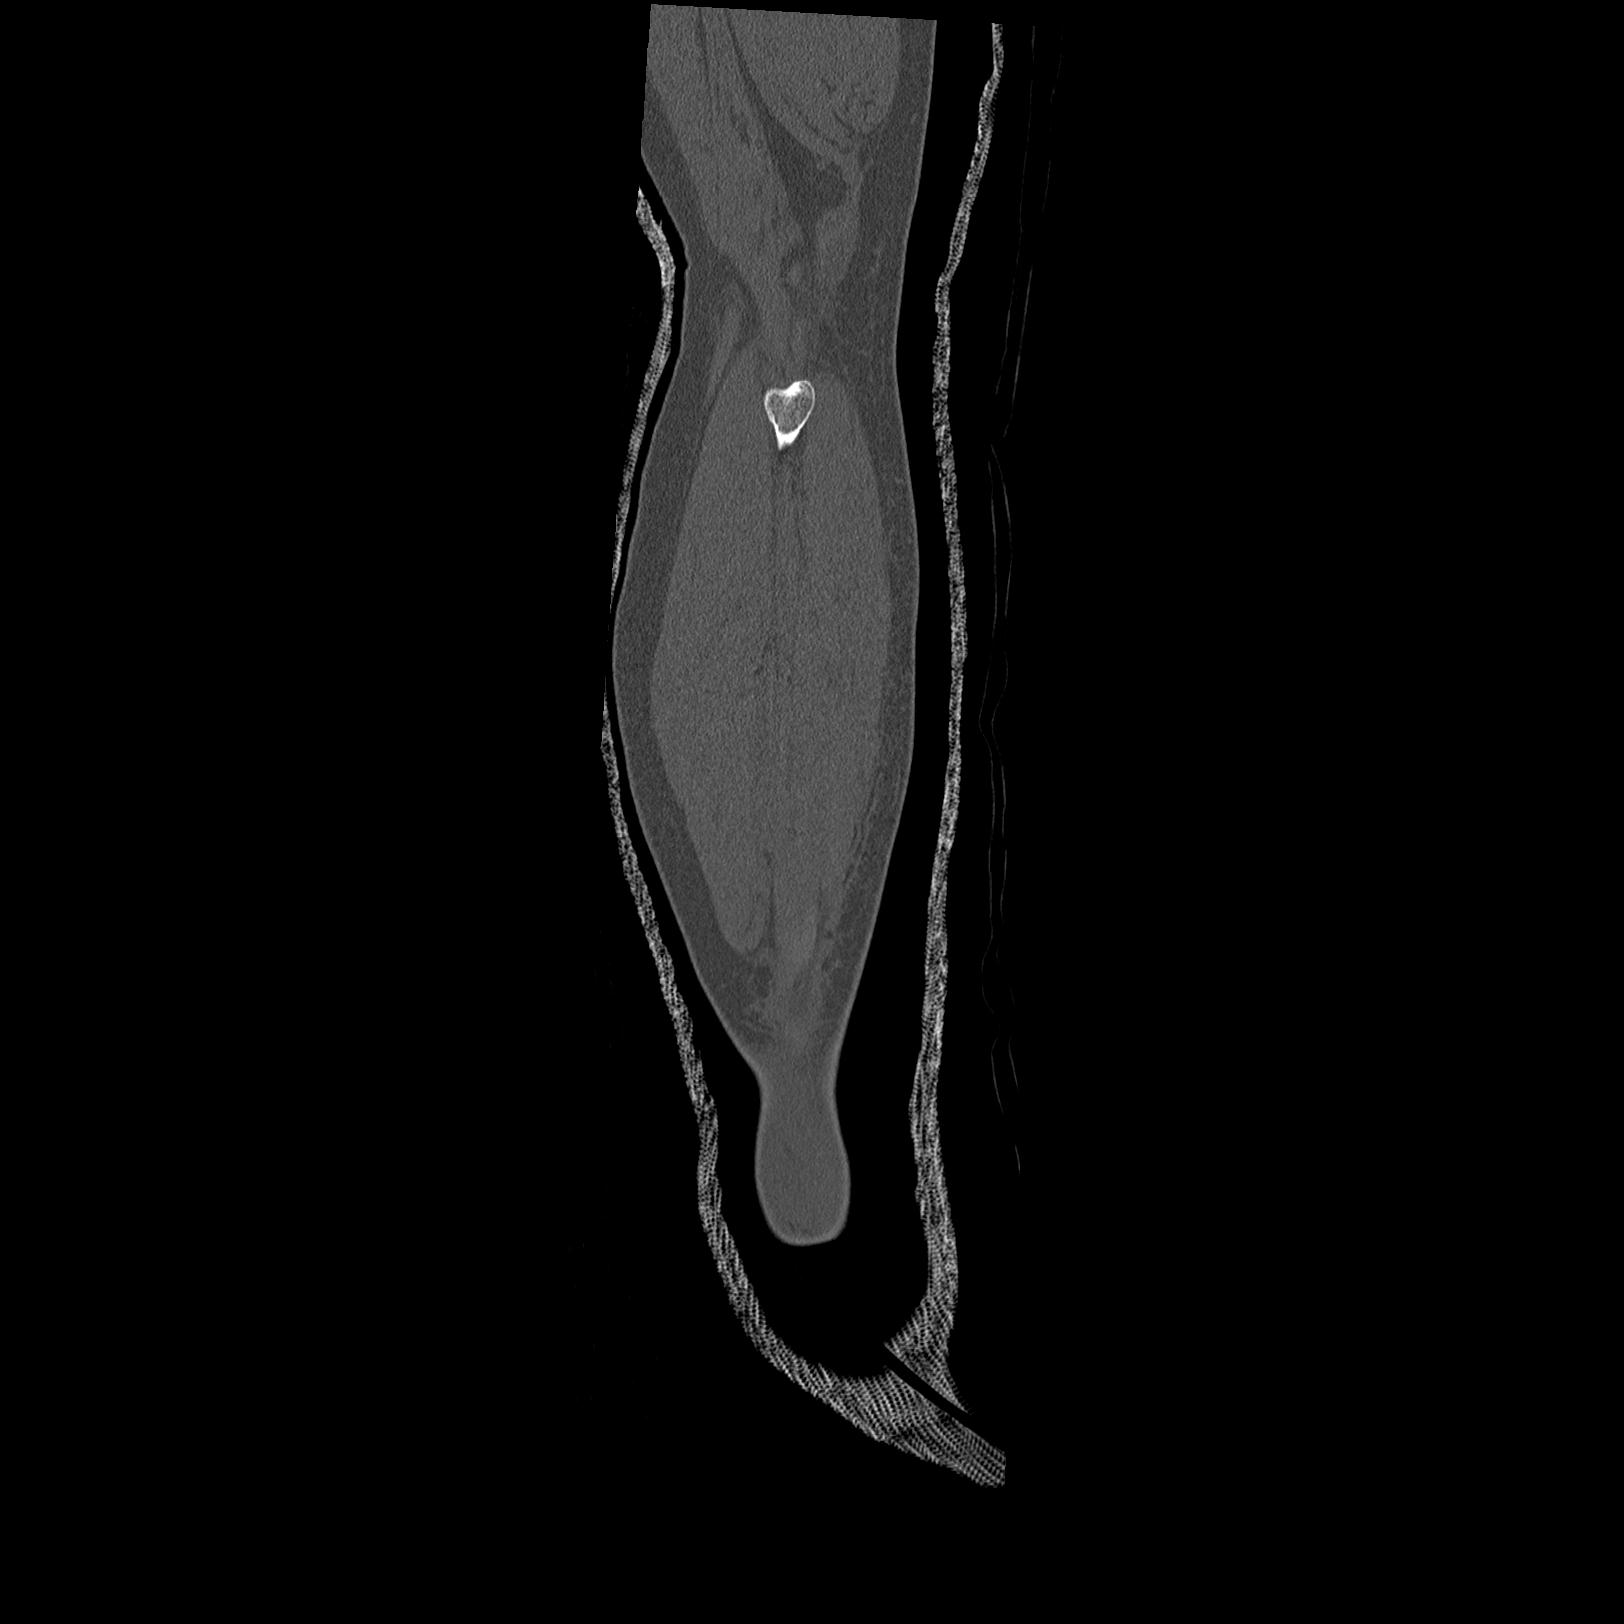

102803 1/12(キウスなし) 1/27 左下腿 4R 30歳女性 左脛骨軸内釘